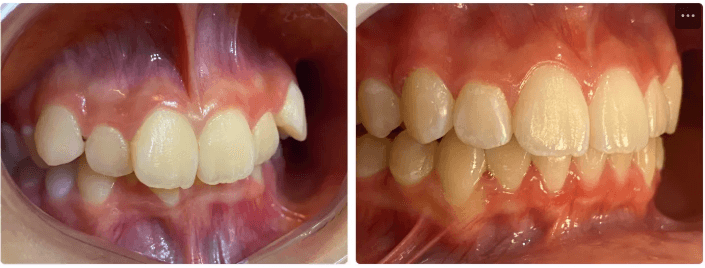

Correções de classe:

A correção de classe com alinhadores pode ser feita através de uma distalização sequencial ou por mesialização sequencial (Você pode conhecer um pouco sobre essas movimentações em Padrões de movimentação com os alinhadores) . Sempre é necessário mecânicas elásticas para tratamentos que envolvem correções de classe.

Tratamentos que envolvem correção de classe são tratamentos longos e que exigem cooperação do paciente pelo uso dos elásticos, o que deve ser conversado antes do início do tratamento. Casos de correção de meio dente ou mais ( no sentido anteroposterior) são indicações para Plano ez24

O alinhador pode fazer compensação de Classe II e Classe III esquelética, mas não substitui ortopedia ou cirurgia.